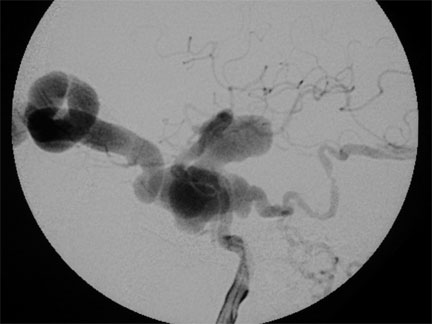

Antes del tratamiento por embolización de fístula carótidocavernosa

Instantes d espués de la embolización de la fístula carótido-cavernosa